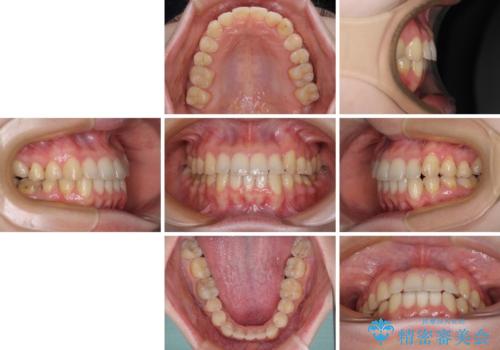

【モニター】1本欠損した下顎前歯と上顎の八重歯 ワイヤー装置で楽して矯正治療

思っていた以上に上顎歯列を後方に移動させることができ、すっきりとした口元に仕上げることができました。

- 八重歯を気にして来院された患者様です。

診査を行ったところ、下顎前歯が1本欠損しており、下顎歯列が上顎よりも小さくなっていることで、上顎にデコボコが生じていました。

口元を見ると抜歯をして突出感を改善するような状態ではなかったため、上顎歯列のデコボコを整えて、歯列全体を後方に移動させることでバランスを取ることとしました。